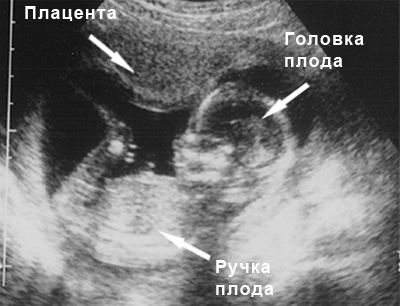

УЗИ: 16-ая неделя беременности

На данном этапе беременности ультразвуковое исследование проводит измерения плаценты. В настоящее время ее размер составляет около 18 миллиметров. Пуповина уже полностью выполняет свою функцию, обеспечивая плод необходимыми питательными веществами и кислородом. Ребенок начинает проявлять рефлекс икоты. На 16-й неделе беременности можно с уверенностью установить пол будущего малыша.